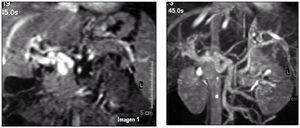

Una niña de 6 años, en el contexto de un cuadro febril de 3 días de evolución, presenta melenas y vómitos en poso de café con dolor abdominal. Exploración: peso, 18 kg (P3); talla, 114 cm (P25); frecuencia cardíaca, 180 lat./min; frecuencia respiratoria, 20 resp./ min, y presión arterial, 102/60 mmHg. Palidez cutáneo-mucosa. Taquicardia rítmica, soplo sistólico II/VI. Abdomen blando, doloroso difusamente a la palpación profunda y esplenomegalia de 3 cm. El resto es normal. Hemograma: leucocitos, 5.080/μl (fórmula normal); hemoglobina, 6,5 g/dl; hematocrito, 18,5 %; plaquetas, 136.000/μl. Urea, 30 mg/dl; glucosa, 95 mg/dl; creatinina, 0,5 mg/dl; proteínas totales, 5,2 g/dl; fibrinógeno, 298 mg/dl. GOT, 40 U/l; GPT, 19 U/l. Coagulación normal. Ecografía abdominal: aumento de la vascularización del hilio hepático con imagen de aspecto varicoso. Troncos principales con flujos venosos que confluyen en la vena esplénica con algunos vasos gruesos que están relacionados con la circulación de la curvatura menor gástrica. Tronco celíaco normal e imagen de arteria hepática entre vasos del hilio. Angiografía por resonancia magnética (RM) (fig. 1A y B): canales vasculares serpiginosos en la localización de la vena porta, esplenomegalia y varices adyacentes al polo superior del bazo con drenaje a vena mesentérica superior y vena renal izquierda (cortocircuito).

Figura 1. Angiografía por resonancia.A)Imagen axial potenciada en T1 con contraste. Se observan los canales vasculares serpiginosos en la localización de la vena porta, indicativo de cavernomatosis portal. Presencia de áreas hipotensas e hipertensas debido a las distintas velocidadesde flujo y canales trombosados.B)Imagen coronal en proyección de máxima intensidad. Se observa toda la circulación portal, las varices adyacentes al polo superior del bazo con drenaje a vena mesentérica superior y vena renal izquierda (cortocircuito). Presencia de esplenomegalia (9,7 cm de diámetro máximo). La vena cava inferior y las venas suprahepáticas no presentan anomalías.